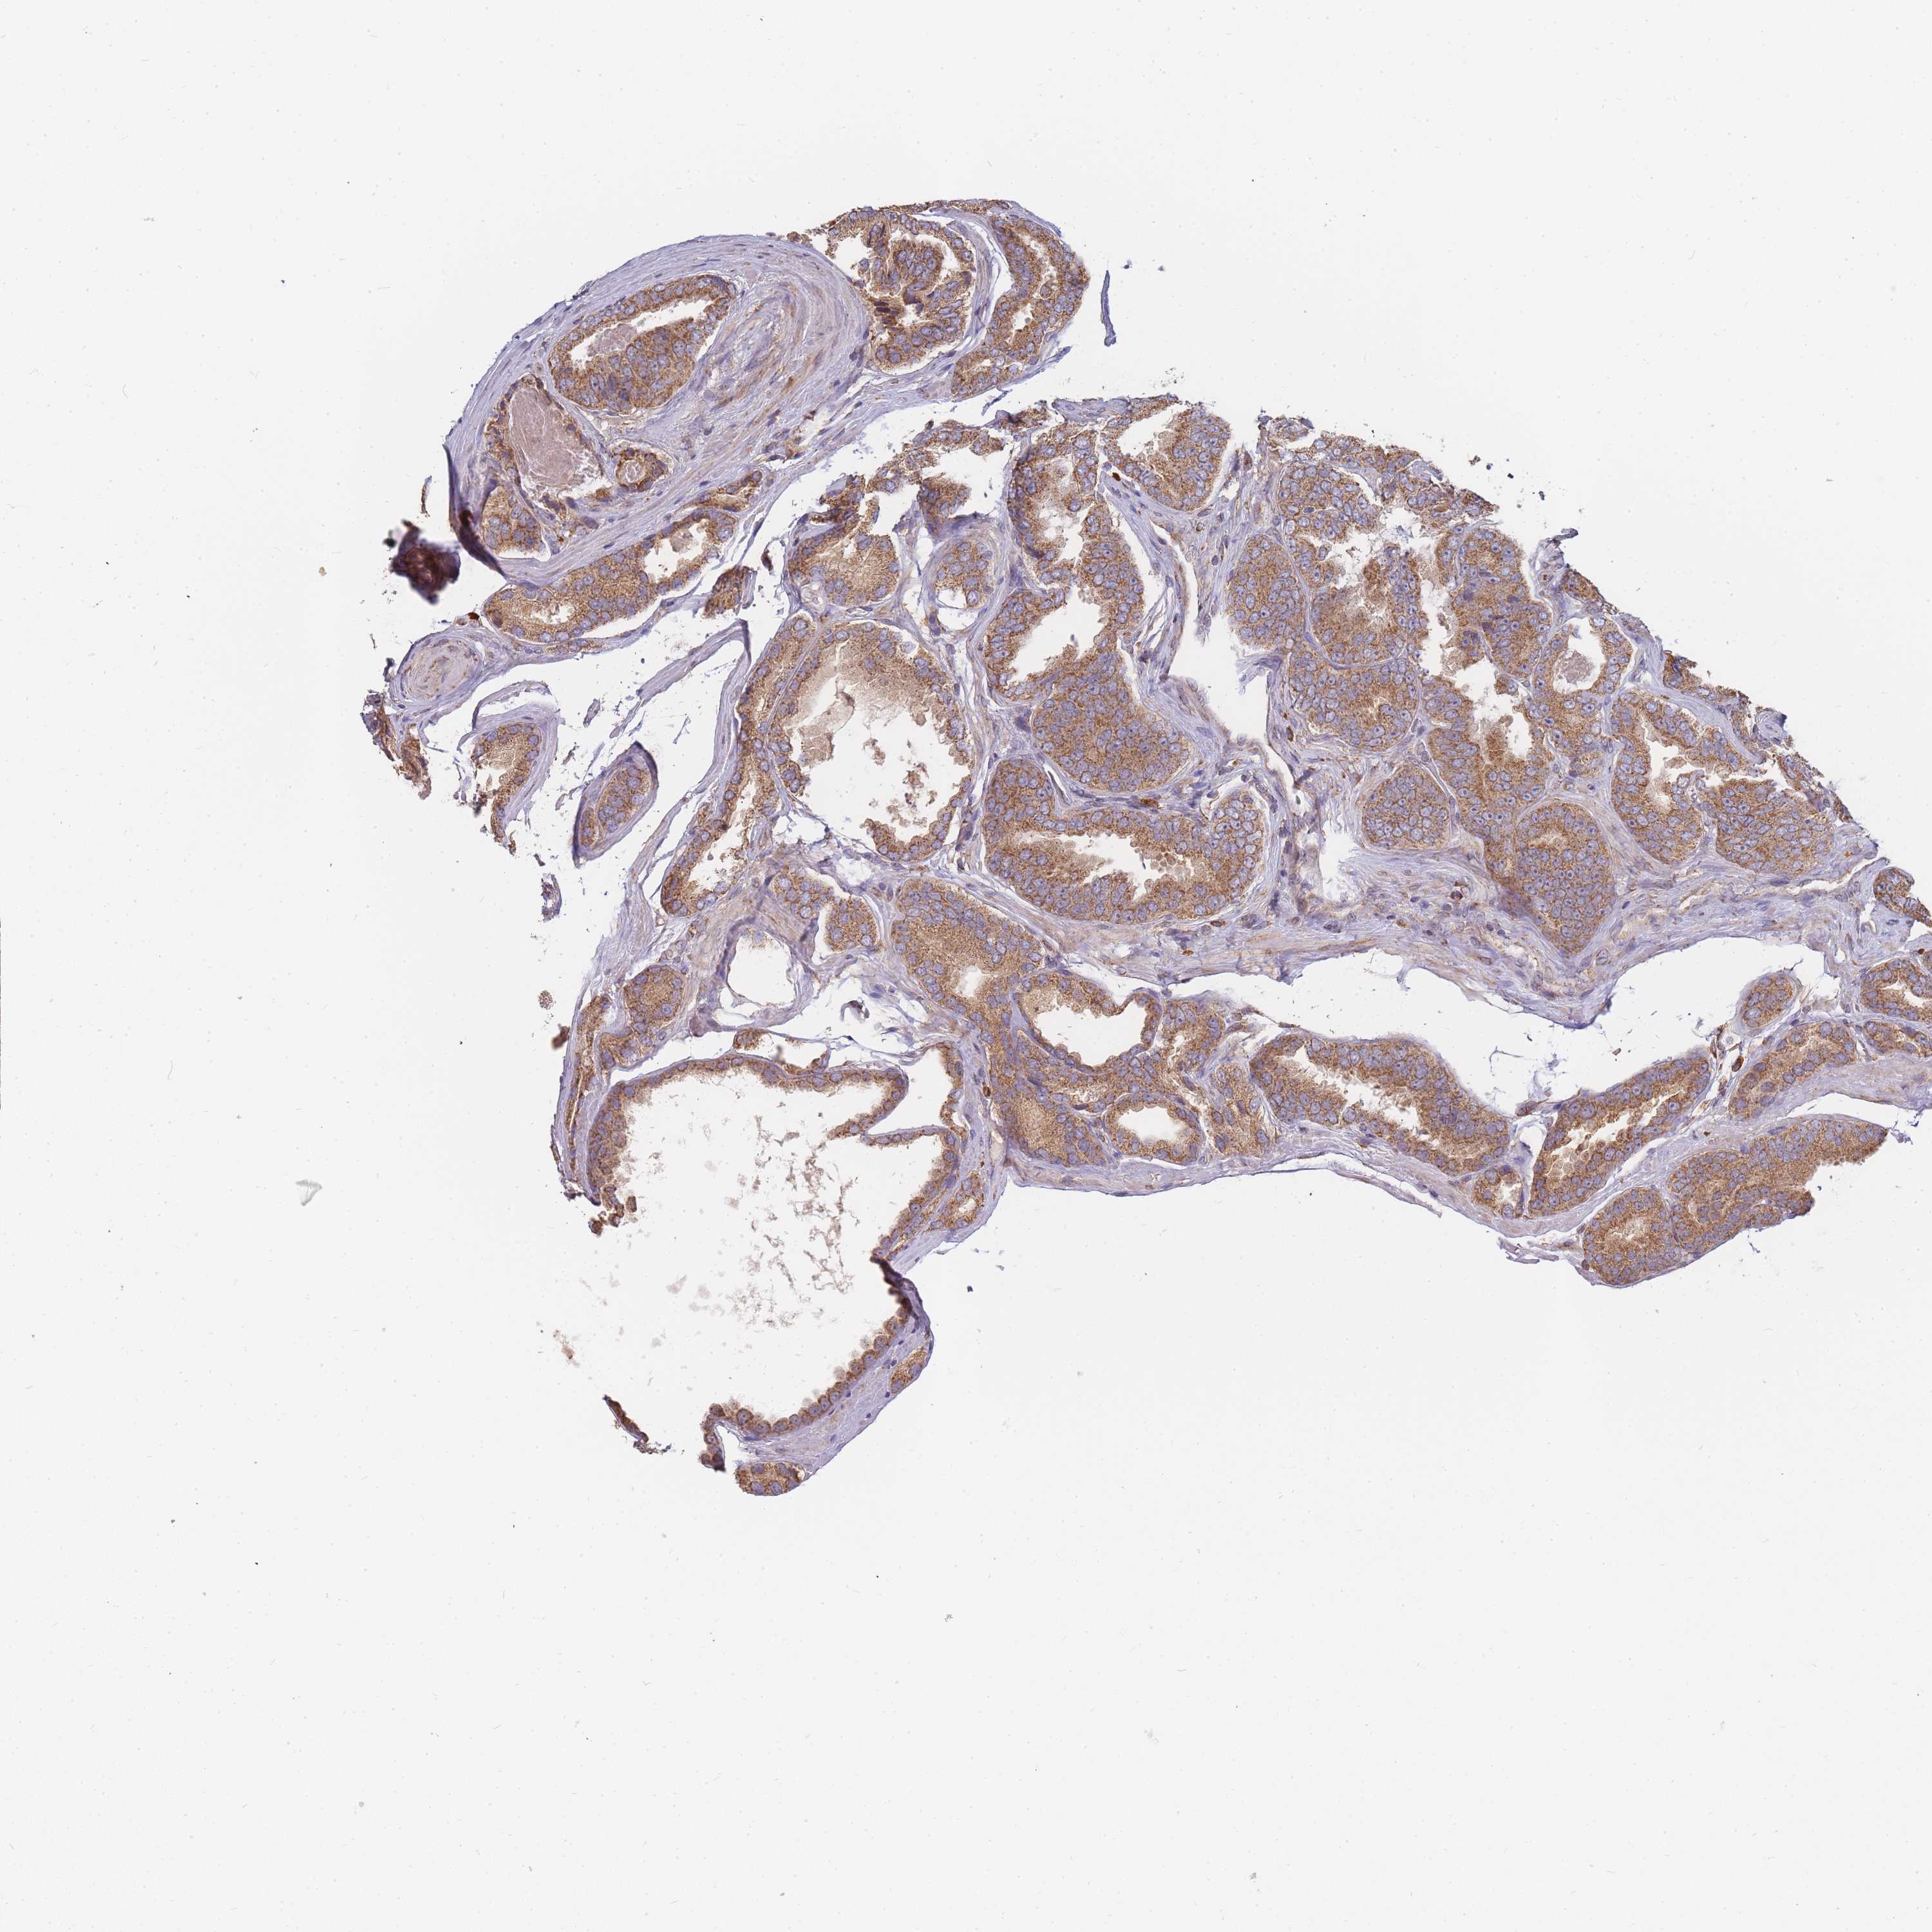

PROSTATE CANCER - Protein expressioni

A mouse-over function shows sample information and annotation data. Click on an image to view it in a full screen mode. Samples can be filtered based on level of antibody staining by selecting one or several of the following categories: high, medium, low and not detected. The assay and annotation is described here.

Note that samples used for immunohistochemistry by the Human Protein Atlas do not correspond to samples in the TCGA dataset.

Antibody stainingi

Antibody staining in the annotated cell types in the current human tissue is reported as not detected, low, medium, or high, based on conventional immunohistochemistry profiling in selected tissues. This score is based on the combination of the staining intensity and fraction of stained cells.

Each image is clickable and will lead to virtual microscopy that enables deeper exploration of all samples and also displays staining intensity scores, fraction scores and subcellular localization as well as patient and tissue information for each sample.

Antibody HPA041328

Antibody HPA044225

Staining

High

Medium

Low

Not detected

Intensity

Strong

Moderate

Weak

Negative

Quantity

>75%

75%-25%

<25%

None

Location

Nuclear

Cytoplasmic/membranous

Cytoplasmic/membranous,nuclear

Adenocarcinoma, NOS

Adenocarcinoma, High grade

Adenocarcinoma, Low grade